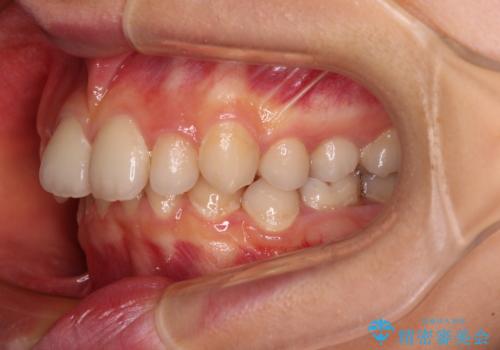

- 後続永久歯の欠損によるスペースと残存乳歯、深い咬み合わせを気にして来院された患者様です。

乳歯を残し、欠損部位のスペースを適正な幅に拡大し、インプラント補綴治療により歯列を整える治療も考えられましたが、ご本人から飛び出している前歯をどうしても引っ込めたいとの要望があったため、残存乳歯ならびに上顎左右第二小臼歯を抜歯して、歯列を整えることとしました。

甚大な咬合力に抵抗して過蓋咬合を改善する必要があり、更には口元が引っ込みすぎることがないように仕上げていく必要もあったため、治療期間は3年を超えましたが、当初計画通りの仕上がりで治療を終えることができました。